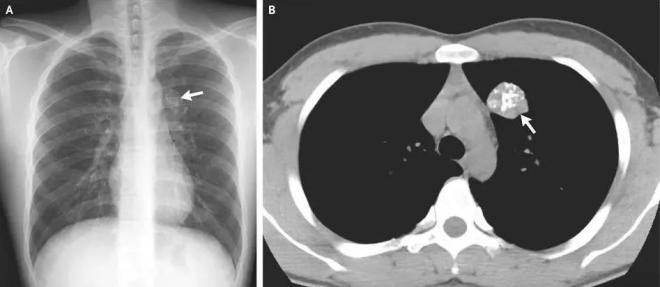

体检报告上的“钙化”,是什么意思?事实上,在X线片、CT、钼靶、超声报告中,常常会出现“钙化”“钙化灶”的字样。据生命时报,钙化,指人体内的钙离子以磷酸盐或碳酸盐形式,发生沉积的过程。很多钙化是在人体病变修复过程中形成的,整个过程和伤口愈合结疤类似。通常表现为钙盐沉积在受损组织中,使这些组织变得坚硬。

人体绝大部分组织和器官内都可能出现钙化,比如头颅的脑膜、基底节区,胸部的肺、肋软骨、胸骨剑突,腹部的肝脏、肾脏,以及甲状腺、乳腺和前列腺等腺体,还有遍布身体的大多数动脉和静脉血管。钙化存在的广泛性也使得它成为体检和平时检查中影像学报告上的“常客”。钙化不是疾病,而是体征

航空总医院影像科副主任申太忠介绍:“钙化不是疾病,而是一种体征。”钙化是否影响健康要根据其出现的部位、影像学特点、患者临床表现来确定。

通过检测钙化的发生位置和程度,医生可及时发现和诊断疾病,了解病情进展,评估治疗效果。钙化的发生与多种因素相关。

疾病:某些慢性疾病可能诱发钙化,比如糖尿病长期未得到有效控制,会导致高血糖和代谢紊乱,并影响肾脏对钙的排泄和代谢,引起钙化。疾病的修复和愈合也可能导致钙化,比如结核性肺炎病变区域的组织,就可能在炎症后的修复过程中形成钙化。